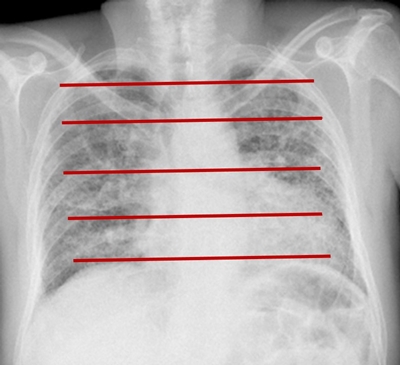

Médicos neumólogos especialistas se encargan de determinar el porcentaje del área total de los pulmones que se ve afectada por la fibrosis. Para esto, realizan una inspección visual de las imágenes de TAC, delimitan el área correspondiente a tejido fibroso, y determinan empíricamente el porcentaje de fibrosis pulmonar (%FP) en cada pulmón de acuerdo a su experiencia y conocimiento de la estructura del parénquima pulmonar sano, vías aéreas, vasculatura y patrón imagenológico de la enfermedad. Las características observadas por los médicos en la TAC son irregularidades intralobulares periféricas y quistes subpleurales con forma semejante a un panal de abejas (Figura 1), lo que significa que las regiones anormales del pulmón con huecos semejando un panal corresponden a regiones con fibrosis pulmonar [1,2].

Para poder evaluar y analizar el desempeño de la estrategia propuesta para el cálculo del %FP, se utilizaron las imágenes de TAC de dos pacientes diagnosticados con fibrosis pulmonar, las cuales fueron proporcionadas por el Instituto Nacional de Enfermedades Respiratorias (INER). En cada paciente, el experto clínico seleccionó 5 imágenes bidimensionales a diferentes alturas del pulmón distribuidas de forma equidistante con el objetivo de abarcar toda la región pulmonar (Figura 2). Todas las imágenes en 2D de TAC tienen una dimensión de 512x512 pixeles, con una dimensión del pixel de 0.6 x 0.6 mm.

Adicionalmente a las opciones localizadas en los menus de la parte superior izquierda de la interfaz, se optó por colocar una serie de botones numerados que permiten calcular de una manera más intuitiva el %FP. El primer botón, esta etiquetado como “Cargar Imagen” el cual permite seleccionar y visualizar el archivo NiFTI de la imagen TAC original. Un segundo botón permite cargar una máscara del pulmón sano o diseñar la máscara de forma manual; esta máscara es la que se utiliza como referencia del 100 % del área del pulmón. El tercer botón sirve para realizar la segmentación de la imagen; en este paso se despliega primero un cuadro de diálogo que permite introducir los valores deseados para cada parámetro del algoritmo y después se ejecuta la segmentación sobre la rebanada seleccionada. Al finalizar, se muestran en diferentes áreas de trabajo, la imagen segmentada y la imagen de diferencia. Después utilizando el botón de “dibujar área de fibrosis” es posible definir la ROI que delimita la región con fibrosis; éste procedimiento es similar a la delimitación usualmente realizada por el médico tal y como se ejemplifica en la Figura 1 (línea roja). Por último, para completar el cálculo se debe utilizar el quinto botón “calcular porcentaje de fibrosis”, el cual despliega un cuadro de diálogo con el valor del %F P estimado.